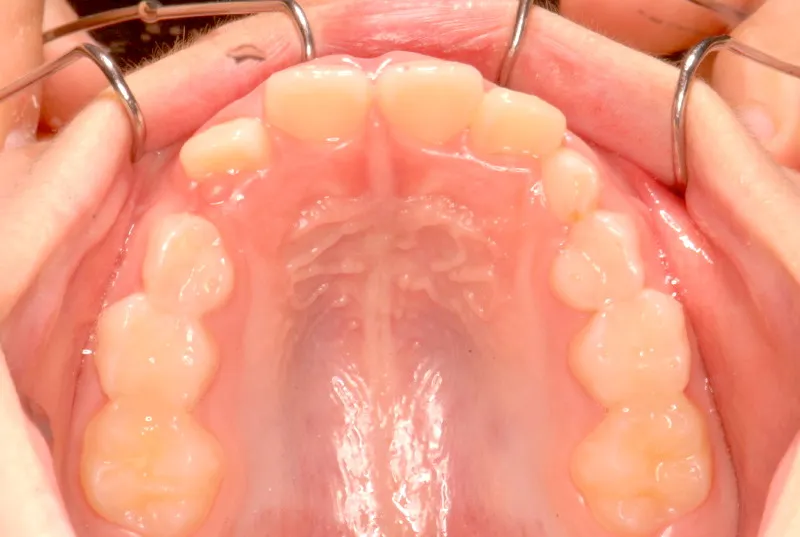

初診時年齢 小学校3年生 (男性) 主訴 前歯がゆがんでいる・ガタガタ

診断名 叢生・交叉咬合 装置名

上下の幅が狭くガタガタに生えています。

乳歯があるうちはオリジナル矯正装置を使用しました。

永久歯に生え変わってからはマルチブラケット装置を使用し、噛み合わせ・見た目をしっかり仕上げました。

治療回数42回、4年6ヶ月の治療期間で矯正治療を終了しました。